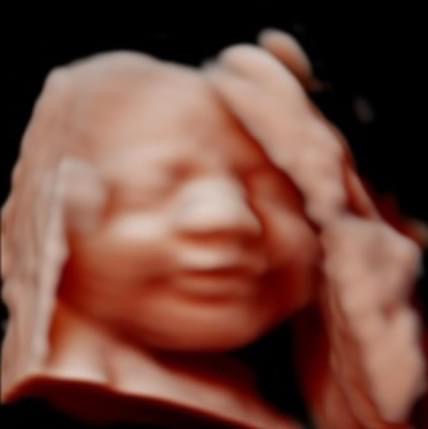

All photos are from our equipment and are of our actual clients.